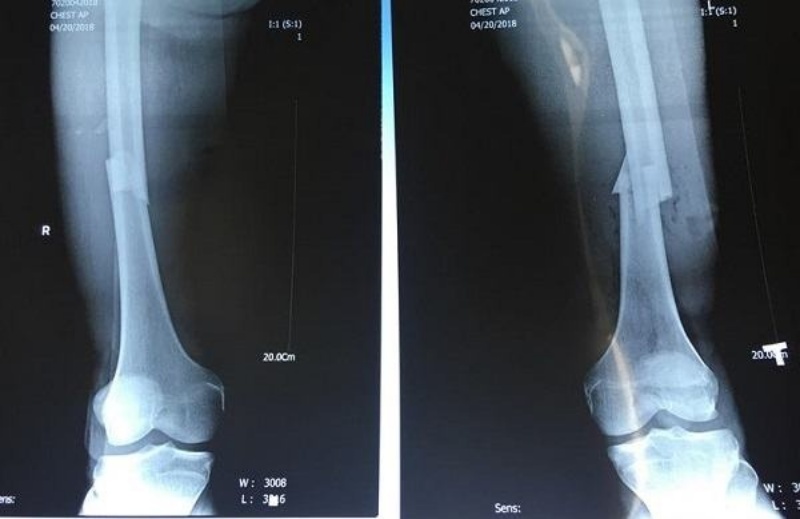

Xương chày khá dài và rất dễ bị gãy. Tình trạng gãy thường xảy ra ở phần xương nằm ở trên khớp cổ chân và dưới khớp gối. Ngoài ra còn có một số tổn thương khác đi kèm.

Gãy xương chày là tình trạng bị rạn hoặc bị gãy một bộ phận hoặc toàn bộ xương chày theo nhiều kiểu với đường gãy khác nhau.

Nguyên nhân gãy xương chày chủ yếu là do tai nạn xe máy, bình thường xương có thể gãy nát thành nhiều mảnh. Hoặc khi chơi thể thao bị té ngã hay trượt patin, trượt tuyết, chơi bóng đá gặp chấn thương mạnh cũng có thể làm gãy thân xương chày. Trường hợp gãy xương do lực xoắn vặn nên đường gãy có thể bị xoắn hoặc bị chéo. Tuy nhiên phổ biến nhất là tình trạng gãy xương chày ngang hình răng cưa.